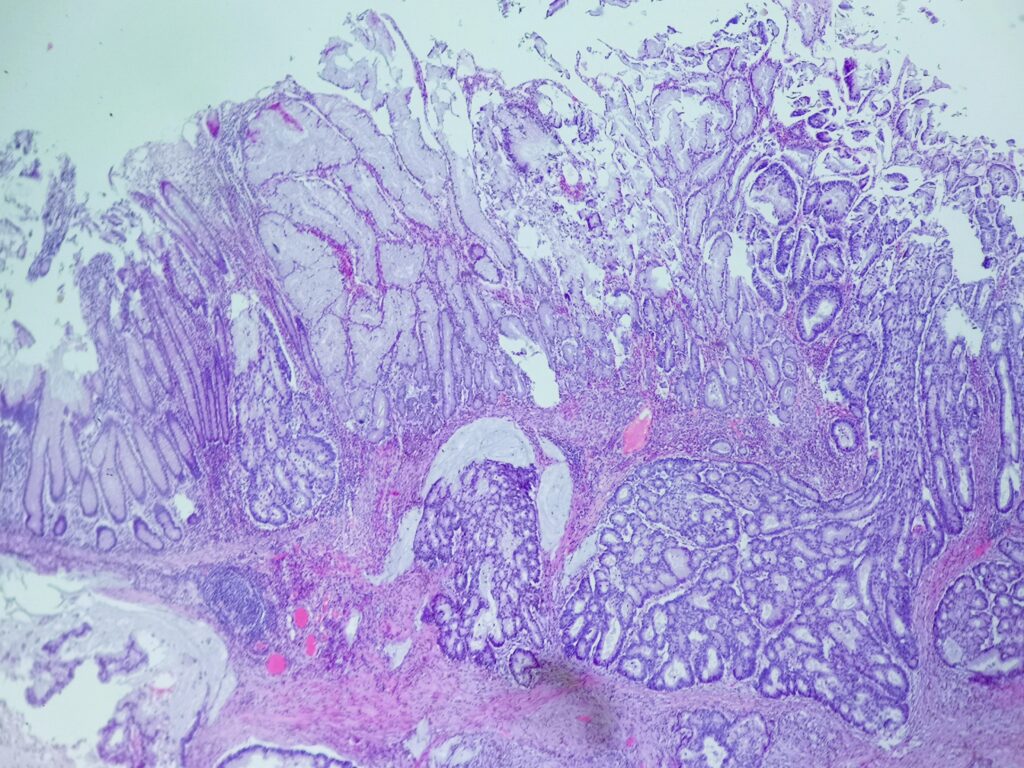

Pacjentka 61 letnia z guzem kątnicy wykrytym w trakcie diagnostyki obecności krwi utajonej w kale. Wykonano prawostronną hemikolektomię.

Do badania makroskopowego nadesłano fragment przewodu pokarmowego długości 55cm zawierający dystalny fragment jelita cienkiego długości 5cm oraz kątnicę, wstępnicę i fragment poprzecznicy. Do jelita przylega fragment sieci wymiarów 30x15x0,5cm. Na przekrojach w kątnicy, w odległości 2cm od zastawki krętniczo- kątniczej oraz około 45 od dystalnej linii odcięcia obecny jest płasko- wyniosły guz wymiarów 5×4,5×1,5cm, który w ocenia makroskopowej jest ograniczony do mięśniówki właściwej, nie nacieka przylegającej tkanki tłuszczowej ani surowicówki.

Obrazy mikroskopowe: